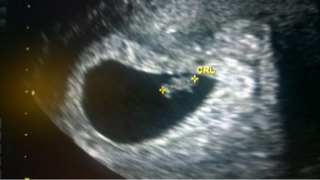

Olot on normaalit, pieni epämääräinen huono olo ajoittain vaivaa. Jollain lailla ei ymmärrä, miten siellä voi vauva kasvaa, kun ei mitään tunnu - mutta kai se voi vähäoireistakin olla. Vielä viikko ja päivä ultraan. Voi hyvän tähden!

Katjusha rv. 6+4